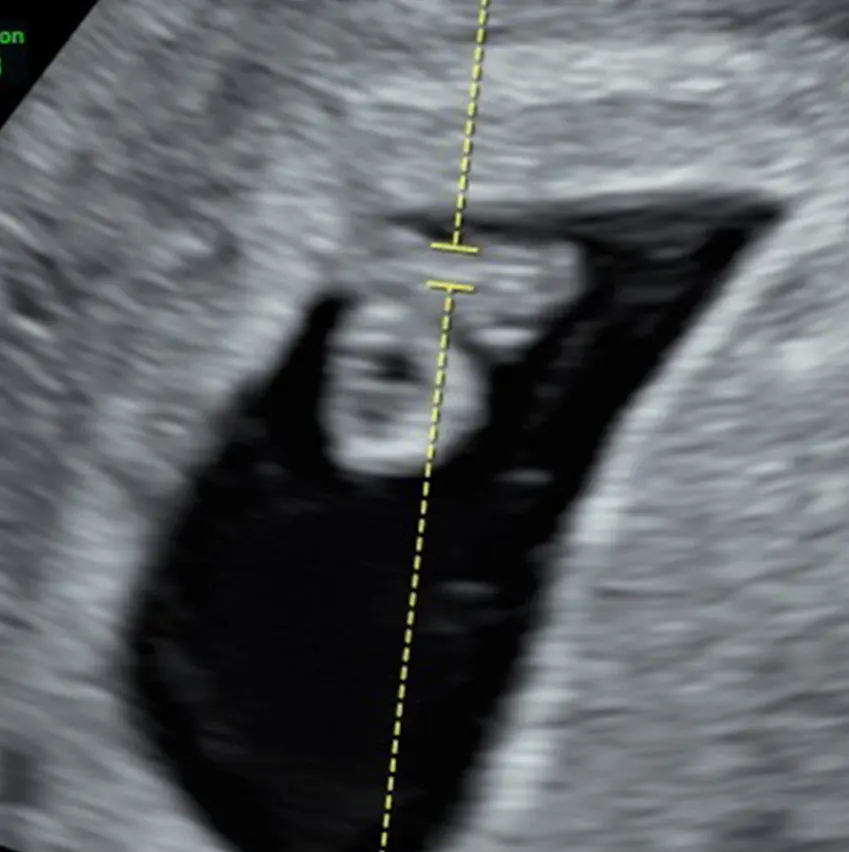

UN DULCE MILAGRO VIENE EN

CAMINO, ACOMPÁÑANOS A

CELEBRAR LA LLEGADA DE

NUESTRO PEQUEÑO TYLER dino gif